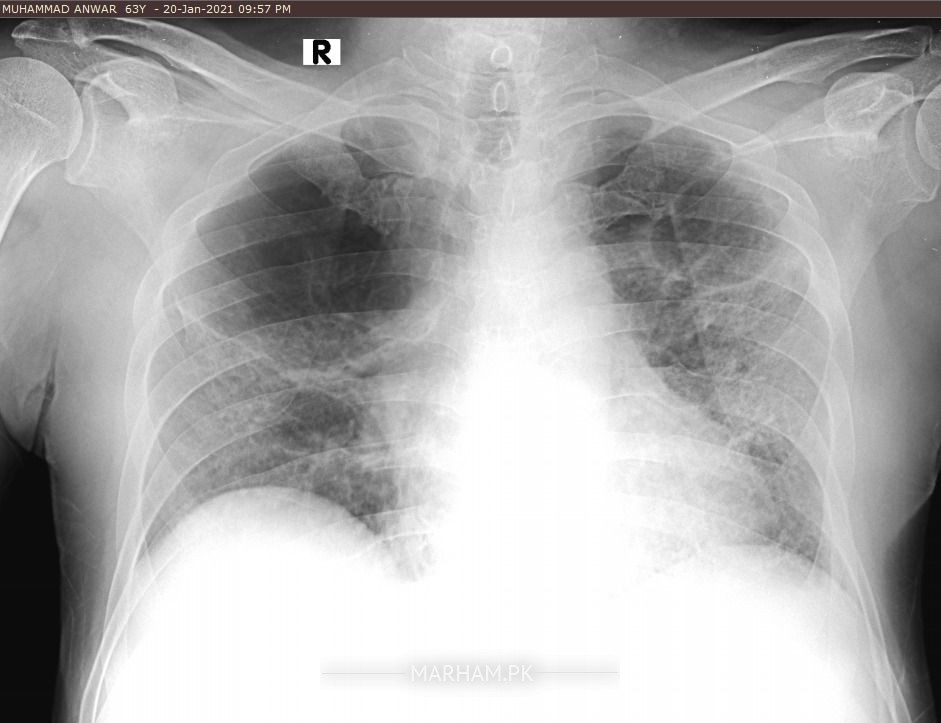

Dear doctors my father is in recovery phase after serious Covid19 today i have done x-ray and ECG of my father just for observe the recovery of inspiration systems re development because from last month he is still on 2ltr oxygen and staying at home with 96/97 sats rate.... Weakness ALHUMDULILLAH recover with good diet and MA SHA ALLAH clinically also very active now so plz doctor give expert opinion on it Medication vibramycine, osnate D, surbux z, loprain, steam 2/3 time in a day pouring and chest physio ongoing good oral intake. If any pulmonologist from rawalpindi Islamabad also pay attention i need your consultation. One x-ray is pervious 26Dec2020 dates mentioned plz review